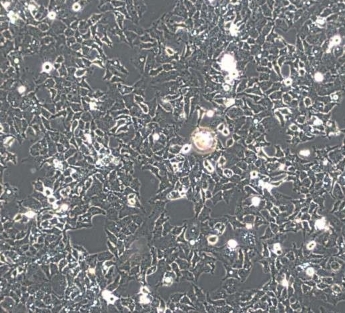

2. 细胞名称:Ishikawa人子宫内膜癌细胞

3. 英文名称:Ishikawa Human Endometrial Adenocarcinoma Cells

4. 组织来源:人子宫内膜腺癌组织

5. 细胞类型:腺癌细胞

6. 生长特性:贴壁细胞

1. 形态特征:上皮细胞样,贴壁生长;细胞形态均一,生长稳定。